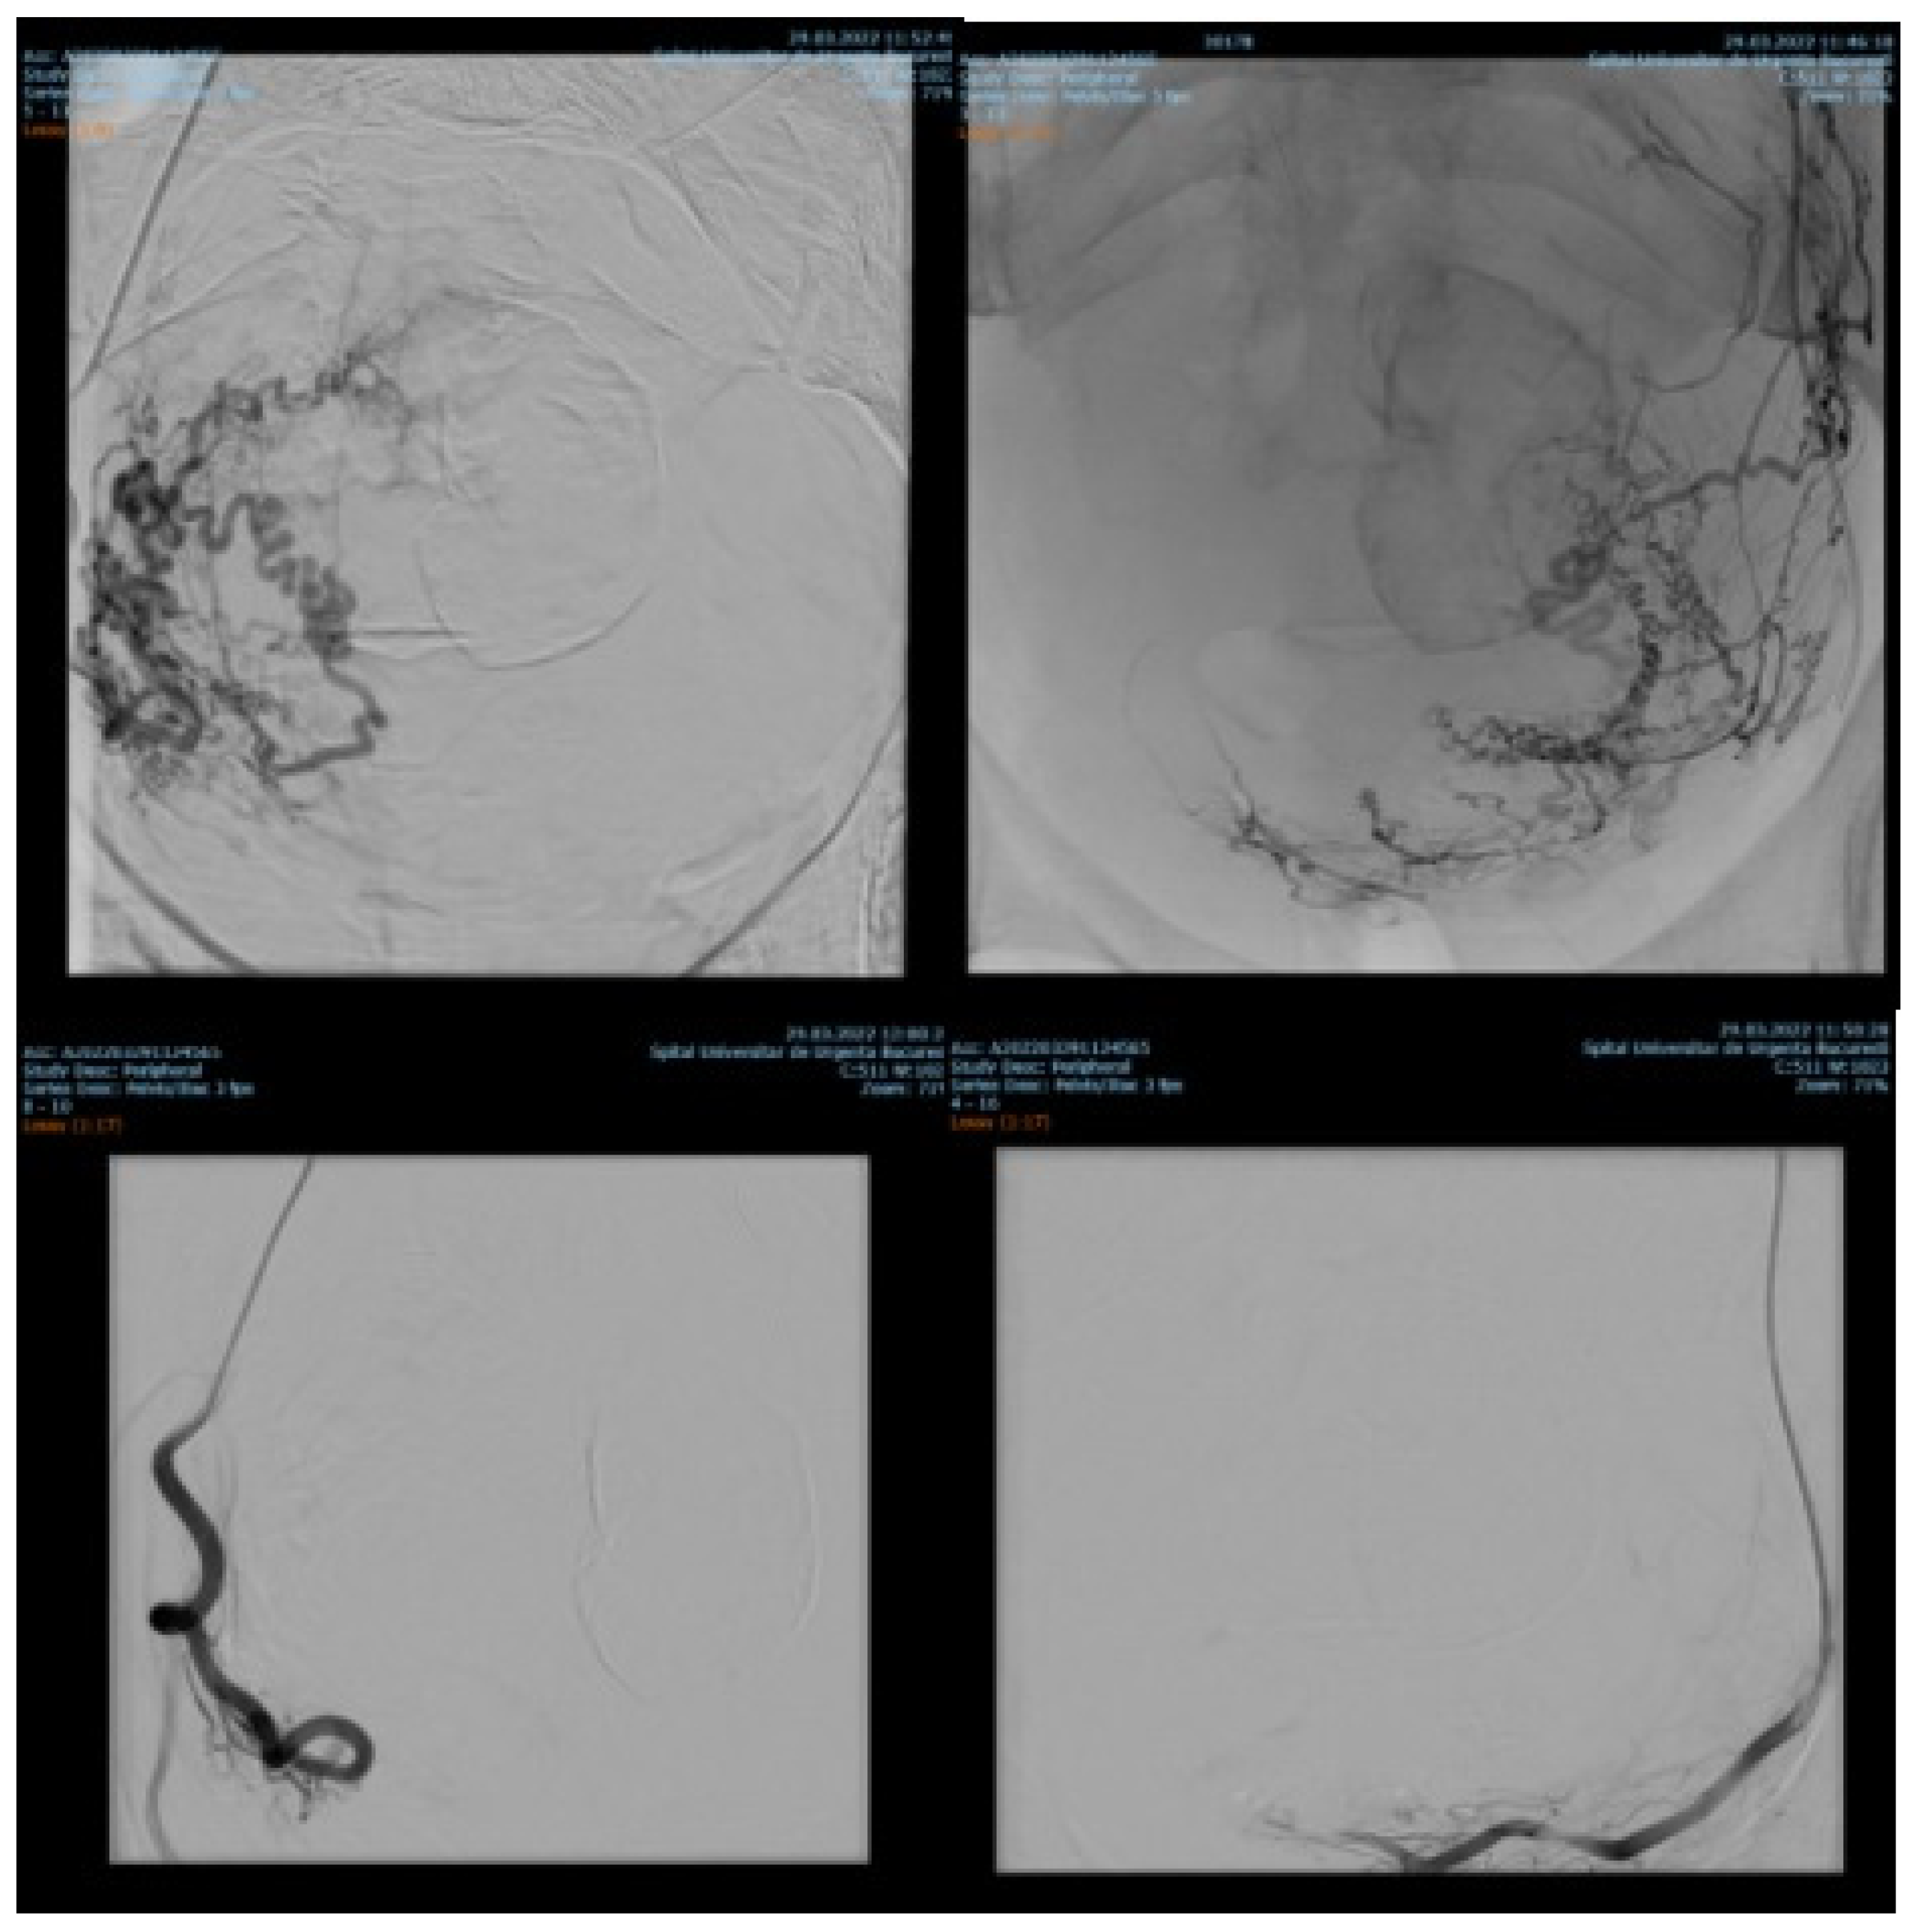

Among 1135 patients, 88.19% presented with uterine leiomyomas (n = 1001), where supra-selective uterine arteries embolization was used. Pre- and postprocedural aspects of uterine artery embolization in a patient with uterine leiomyomas are shown in Figure 1.

Figure 1. Uterine artery embolization in uterine leiomyoma.